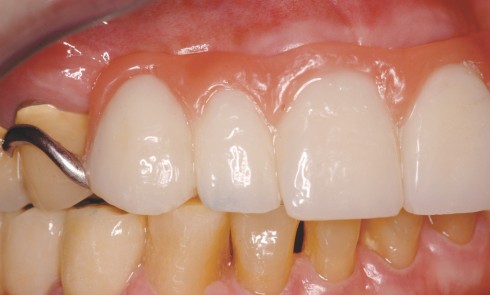

Odontologie restauratrice

Article réservé à nos abonnés Facettes en céramique et gingivectomies : une approche a minima

Le sourire harmonieux est le fruit d’un équilibre complexe impliquant le positionnement des dents, leur couleur, leur forme et leur...